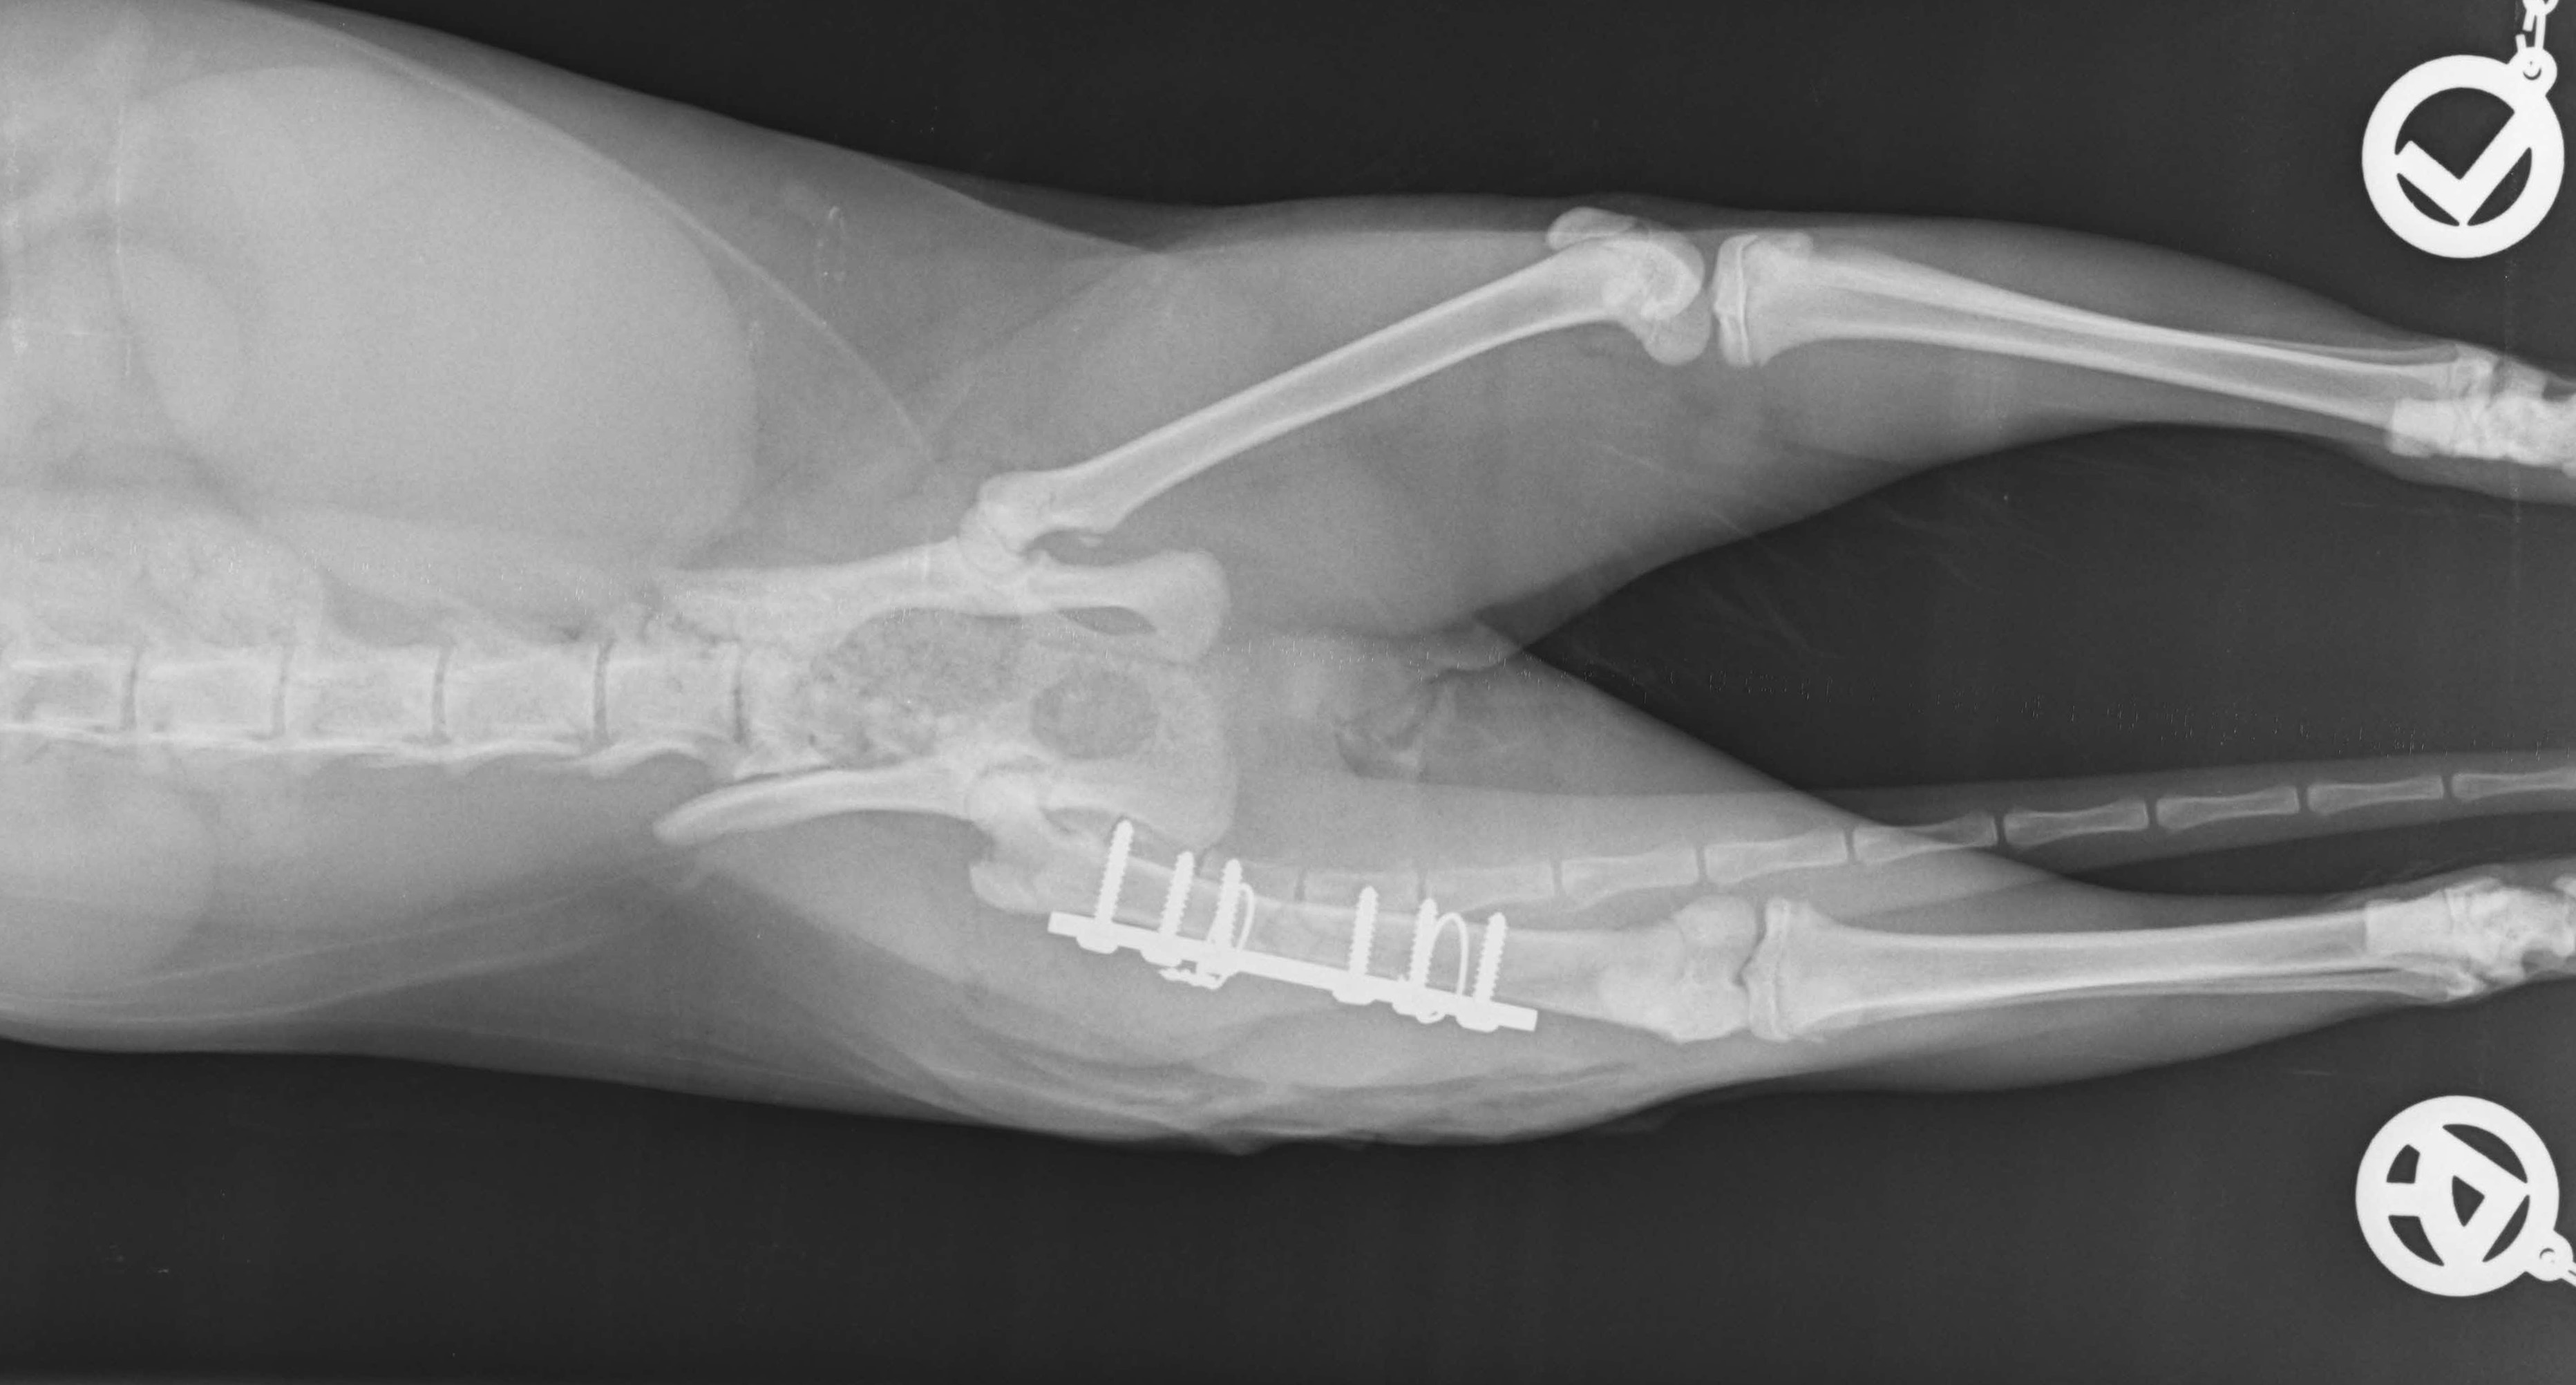

Röntgen, Ultraschall und auch die Endoskopie gehören bei uns zu den bildgebenden Diagnosemethoden, die routinemäßig angewendet werden. Viele Erkrankungen lassen sich erst durch diese weiterführenden Untersuchungen zweifelsfrei feststellen.